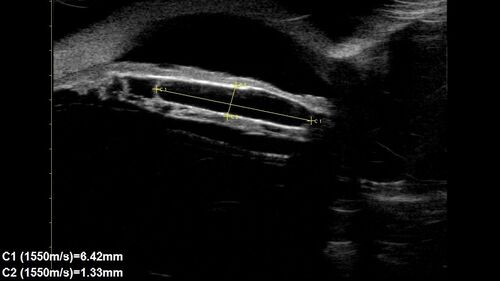

Idiopathic Iris Cyst

85 year old man History of wet AMD OD x 7 years under treatment with Lucentis. VA 20/40 OD, 20/32 OS

PMHx High cholesterol, GERD, COPD, A-Fib,

MEDS: coumadin and ASA and others

Idiopathic Iris Cyst -UBM